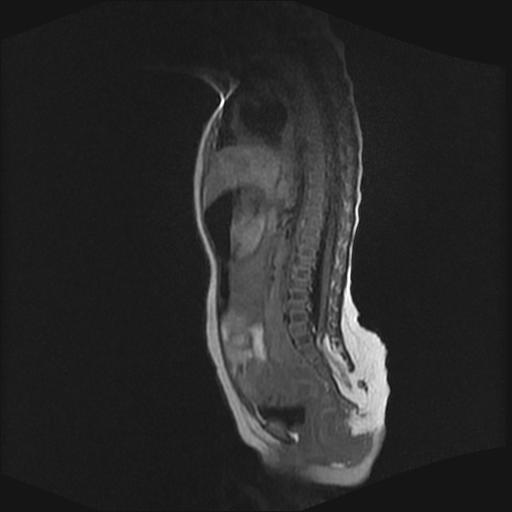

四个月的女婴,ct示脊膜膨出.

脊柱裂、脊膜膨出,请结合临床除外皮毛窦。

脂肪脊髓脊膜膨出

脊柱裂、脊膜膨出